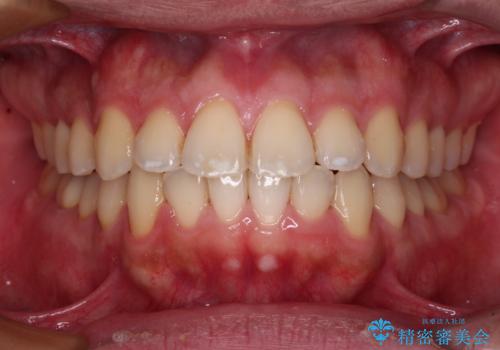

- 八重歯やデコボコをインビザラインで治療したいとのことで来院された患者様です。

インビザライン単体で治療を行うには叢生が強いと判断されたため、事前にワイヤー装置で抜歯矯正を行い、ある程度改善してからインビザラインにて仕上げていくこととしました。